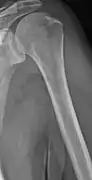

Illustration showing the most common site of bone lesions in vertebrae

Bone pain affects almost 70% of people with multiple myeloma and is one of the most common symptoms.[2]:653[22] Myeloma bone pain usually involves the spine and ribs, and worsens with activity. Persistent, localized pain may indicate a pathological bone fracture. Involvement of the vertebrae may lead to spinal cord compression or kyphosis. Myeloma bone disease is due to the overexpression of receptor activator for nuclear factor κ B ligand (RANKL) by bone marrow stroma. RANKL activates osteoclasts, which resorb bone. The resultant bone lesions are lytic (cause breakdown) in nature, and are best seen in plain radiographs, which may show "punched-out" resorptive lesions (including the "raindrop" appearance of the skull on radiography). The breakdown of bone also leads to the release of calcium ions into the blood, leading to hypercalcemia and its associated symptoms.[23]